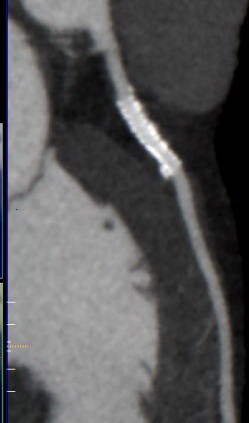

2020 photo courtesy of Dr Shaw, showing stent in LAD and disease in LCX

end view of an artery seen on right side. Below 2020

CTA Imaging for heart disease using a 640 Slice CTA 7. From the 3 photos below you can see kinda see the clarity that the 3 different types of imaging I had done and what each machines produces, unfortunately I still see my disease in the 3rd and best picture, so in 4 years the plaque burden evidently remains about the same, so good news. |

2017, 640 CTA slice machine of my CFX artery Dr. Amar Shah location of Northwell CTA |

2020 curved multi planar images showing stent in LAD(left) and disease in LCX tks Dr. Shaw for great images, end view of arteries are seen on right. |